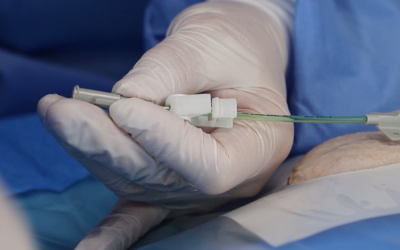

Los PICC de doble y triple luz (Figura 2) se asocian con un aumento de las oclusiones. Dependiendo de la situación clínica, deben preferirse los lúmenes individuales tal y como apuntan las guías de práctica clínica16-19